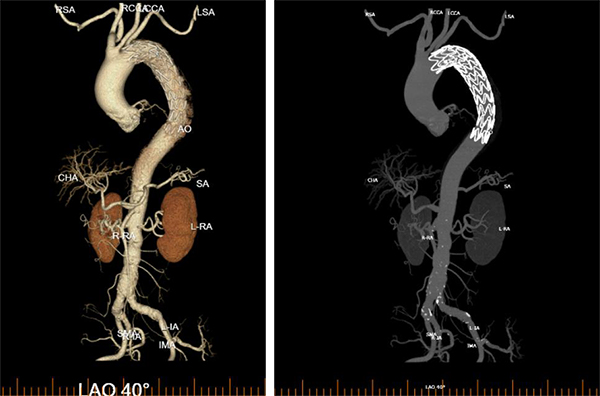

术中,周围血管科团队凭借丰富的临床经验和精湛的手术技艺,精准定位主动脉破口,成功植入覆膜支架,完整修复了撕裂的血管内膜,隔绝了假腔血流。术后造影显示支架位置良好,主动脉破口完全封闭,手术取得圆满成功。